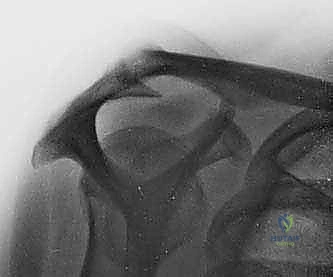

- الأشعة السينية (X-rays): لاستبعاد وجود كسور، وتقييم المسافة تحت الأخرم، ورؤية النتوءات العظمية أو التكلسات التي قد تكون سبباً في قطع الوتر.